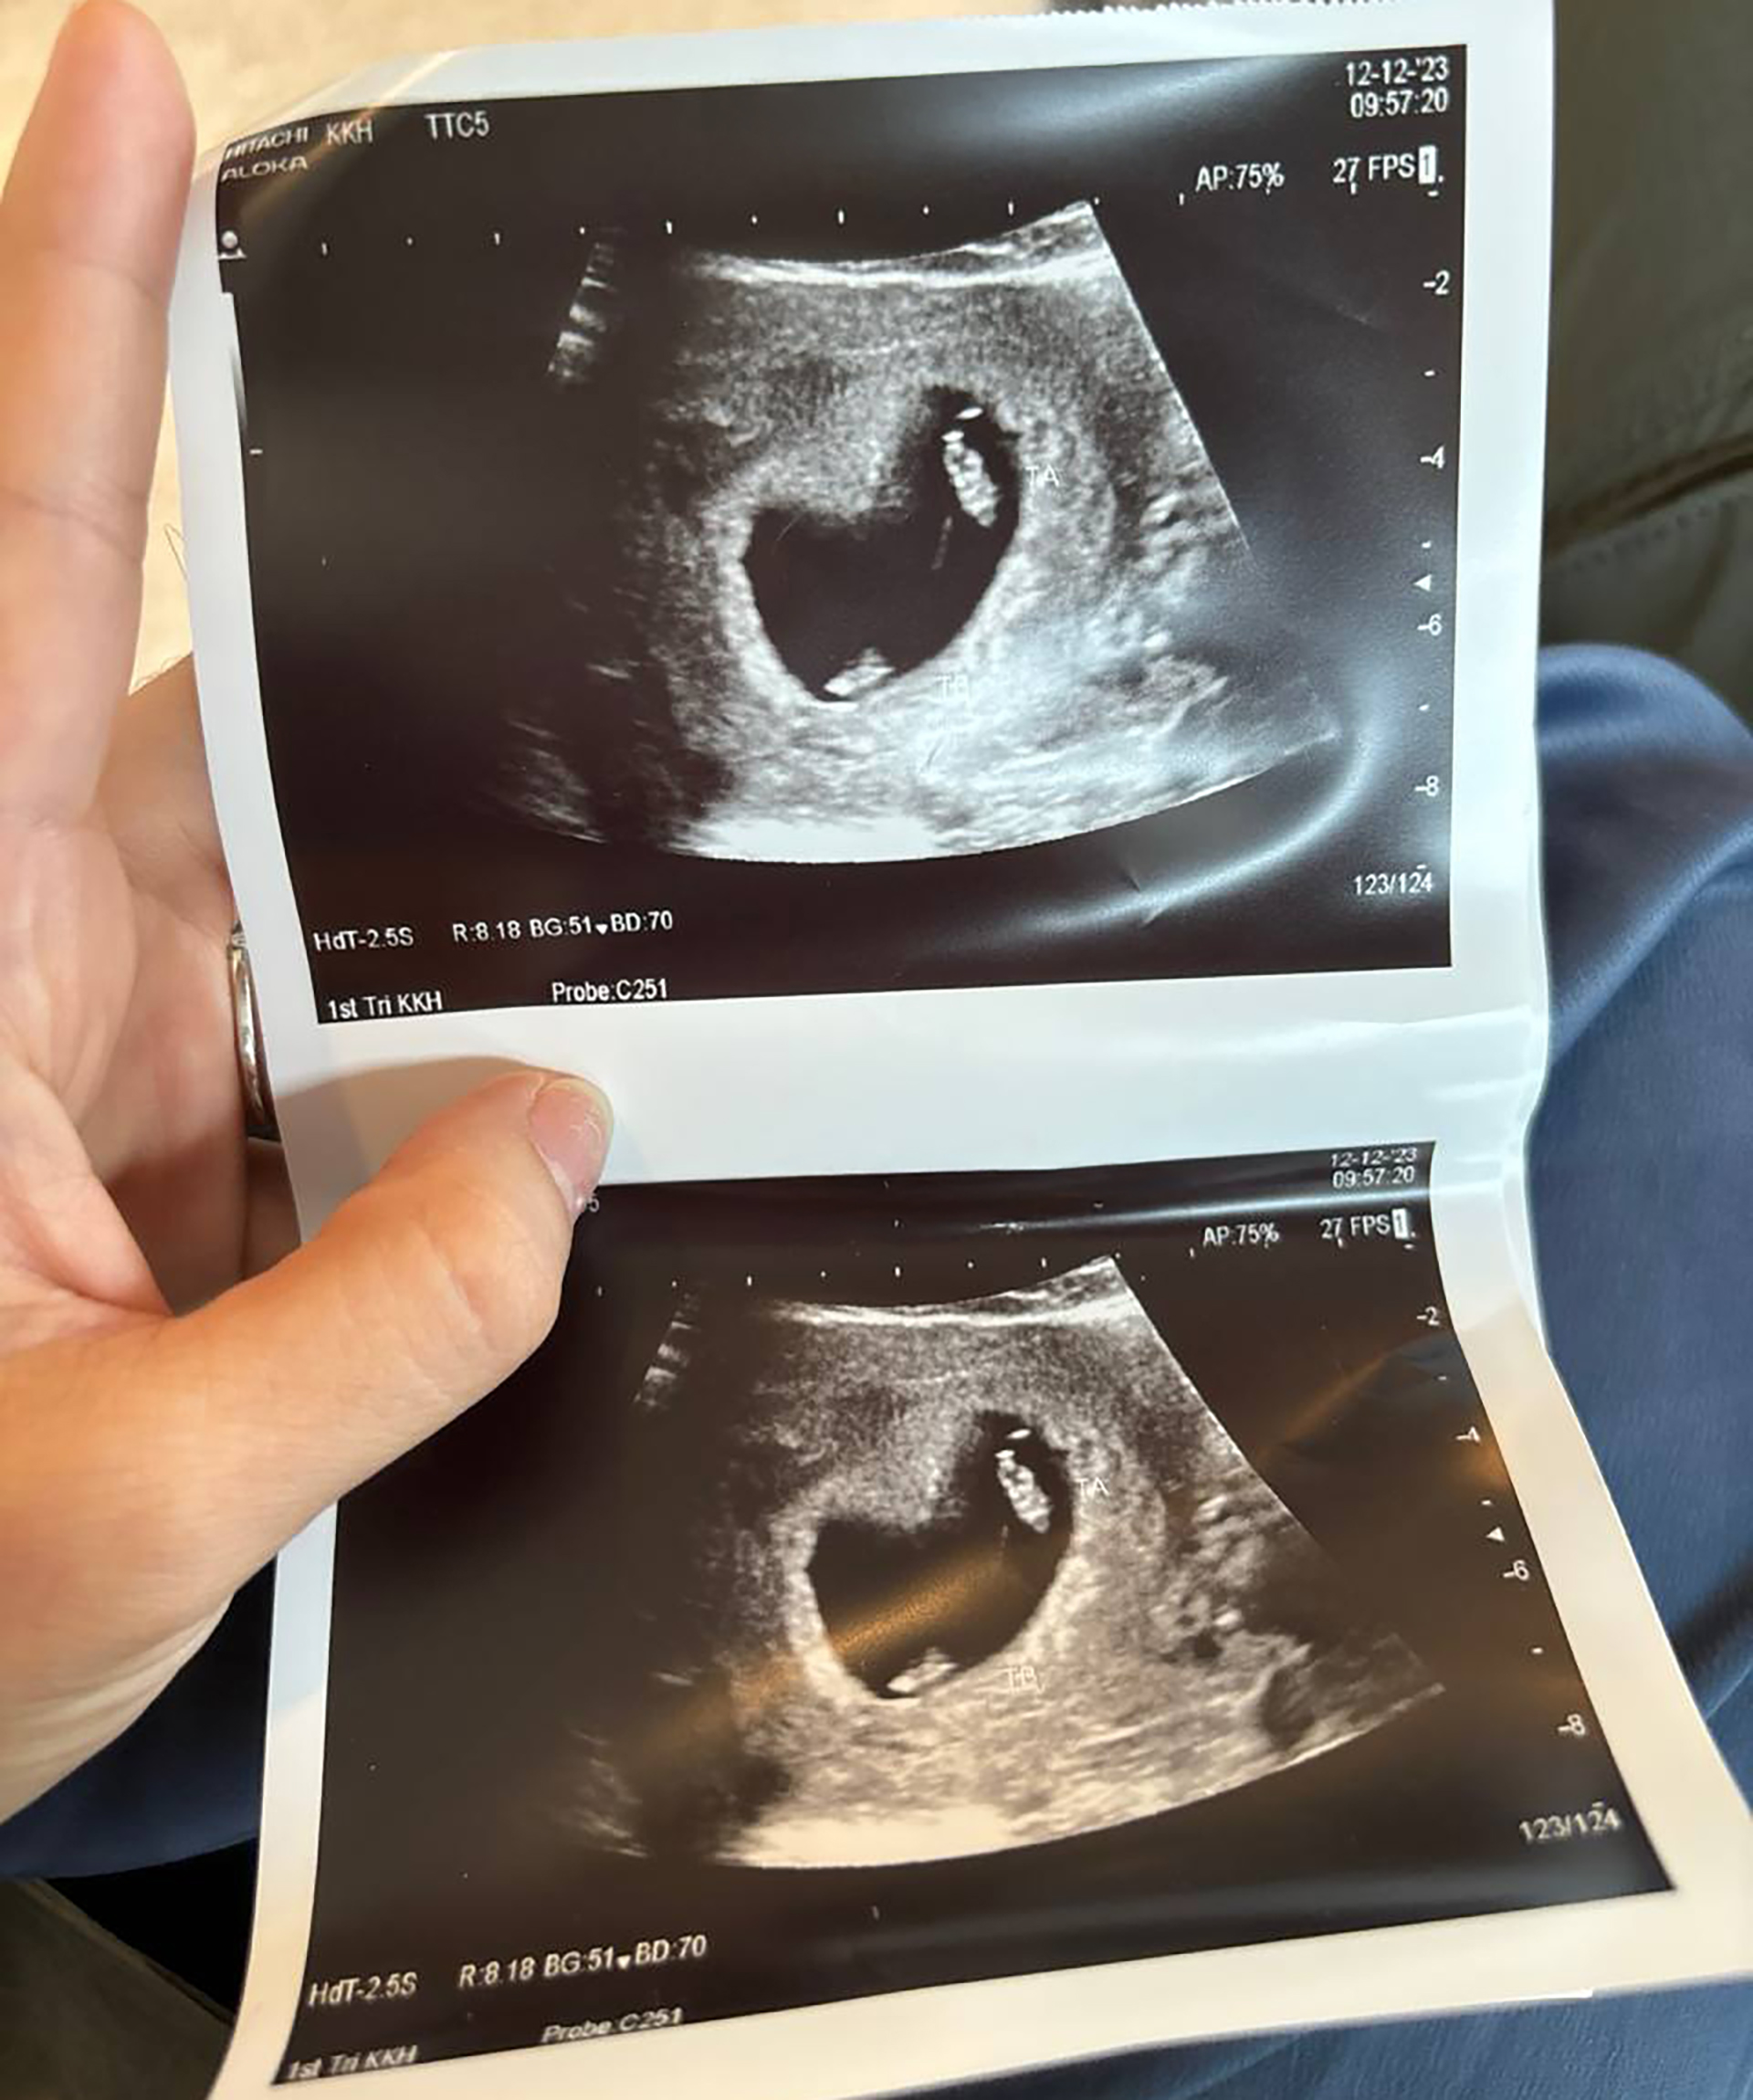

S: Harold's immediate reaction was pure shock; the only word that came out of his mouth was, "Huh?" As for me, the surprise was so overwhelming that I literally lost my breath. The sonographer had to gently ask me to hold still so the scan could be completed because I was hyperventilating! It was one of those life-changing moments where disbelief and excitement collide, and we knew our journey ahead would be beautifully unpredictable.

Since our boys are Monochorionic Diamniotic (MCDA) twins (sharing one placenta but in separate sacs), Sarah was prescribed iron supplements and we had more frequent check-ups, which helped us feel more at peace.